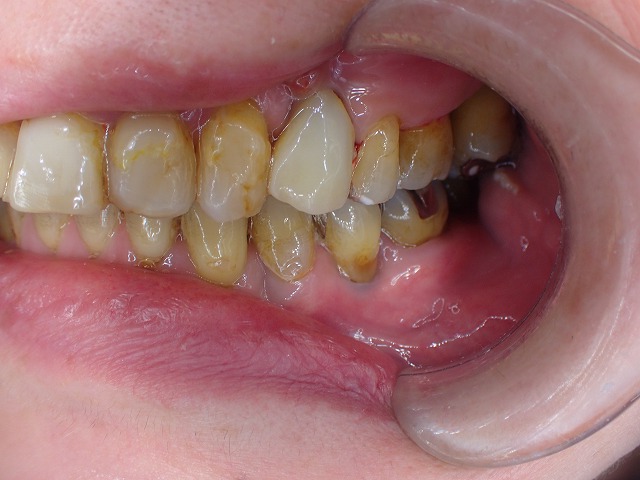

左側

今回は、歯が崩壊したので

CAD/CAM冠を制作しました。